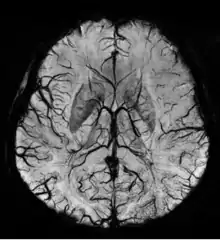

Susceptibility weighted imaging (SWI), originally called BOLD venographic imaging, is an MRI sequence that is exquisitely sensitive to venous blood, hemorrhage and iron storage. SWI uses a fully flow compensated, long echo, gradient recalled echo (GRE) pulse sequence to acquire images. This method exploits the susceptibility differences between tissues and uses the phase image to detect these differences. The magnitude and phase data are combined to produce an enhanced contrast magnitude image. The imaging of venous blood with SWI is a blood-oxygen-level dependent (BOLD) technique which is why it was (and is sometimes still) referred to as BOLD venography. Due to its sensitivity to venous blood SWI is commonly used in traumatic brain injuries (TBI) and for high resolution brain venographies but has many other clinical applications. SWI is offered as a clinical package by Philips and Siemens but can be run on any manufacturer’s machine at field strengths of 1.0 T, 1.5 T, 3.0 T and higher.

SWI uses a fully velocity compensated, RF spoiled, high-resolution, 3D gradient recalled echo (GRE) scan. Both the magnitude and phase images are saved, and the phase image is high pass (HP) filtered to remove unwanted artifacts. The magnitude image is then combined with the phase image to create an enhanced contrast magnitude image referred to as the susceptibility weighted (SW) image. It is also common to create minimum intensity projections (mIP) over 8 to 10 mm to better visualize vein connectivity. In this way four sets of images are generated, the original magnitude, HP filtered phase, susceptibility weighted, and mIPs over the susceptibility weighted images.

The susceptibility weighted image is created by combining the magnitude and filtered phase images. A mask is created from the phase image by mapping all values above 0 radians to be 1 and linearly mapping values from -π to 0 radians to range from 0 to 1, respectively. Alternatively, a power function (typically 4th degree) can be used instead of a linear mapping from -π to 0 to increase the effect of the mask. The magnitude image is then multiplied by this mask. In this way phase values above 0 radians have no effect and phase values below 0 radians darken the magnitude image. This increases the contrast in the magnitude image for objects with low phase values such as veins, iron, and hemorrhage.